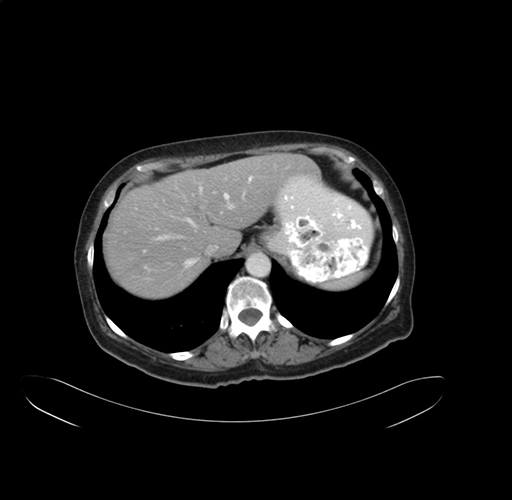

Pre-Chemo: Axial Venous

Axial Venous

Imaging analysis

Based on your CT findings, which issue(s) would give reason for "planned slowing down moment(s)" in this case?

Considering a standard right hepatectomy procedure, what step(s) of the operation would you do differently in this case?